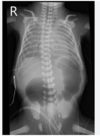

What is the most likely cause of this neonatal pathology? [1]

Osteogenesis imperfecta